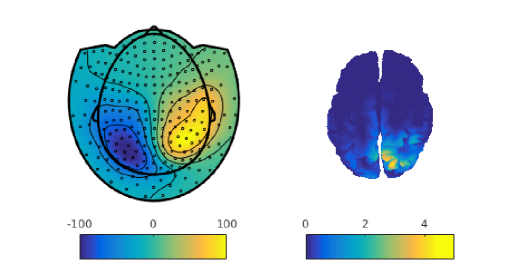

From a practical perspective, it is crucial to understand how the different parts of the brain interact, which is sometimes known as functional connectivity. A possible way to understand these interactions is by analyzing the covariance function associated with the signals describing the cerebral activity of an individual on the brain space (Fransson et al., 2011; Lee et al., 2013; Li et al., 2009). More recently, the interest has shifted from this static approach to a dynamic approach. In particular, for a single individual, it is of interest to understand how these covariance functions vary in time. This is a particularly active field, known as dynamic functional connectivity (Hutchison et al., 2013). Another element of interest is understanding how these covariance functions vary among individuals. In Figure 2, we show the covariance matrices, on the sensors space, computed from the MEG signals of three different subjects.

Consider now sample covariance matrices , each of size , representing different connectivity maps on the sensors space. Three of such covariance matrices, associated with three different individuals, are shown in Figure 2. Recall moreover that we denote with the brain surface template and with the set of subject-specific forward operators, relating the signal at the pre-specified points on the cortical surface with the signal detected on the sensors.